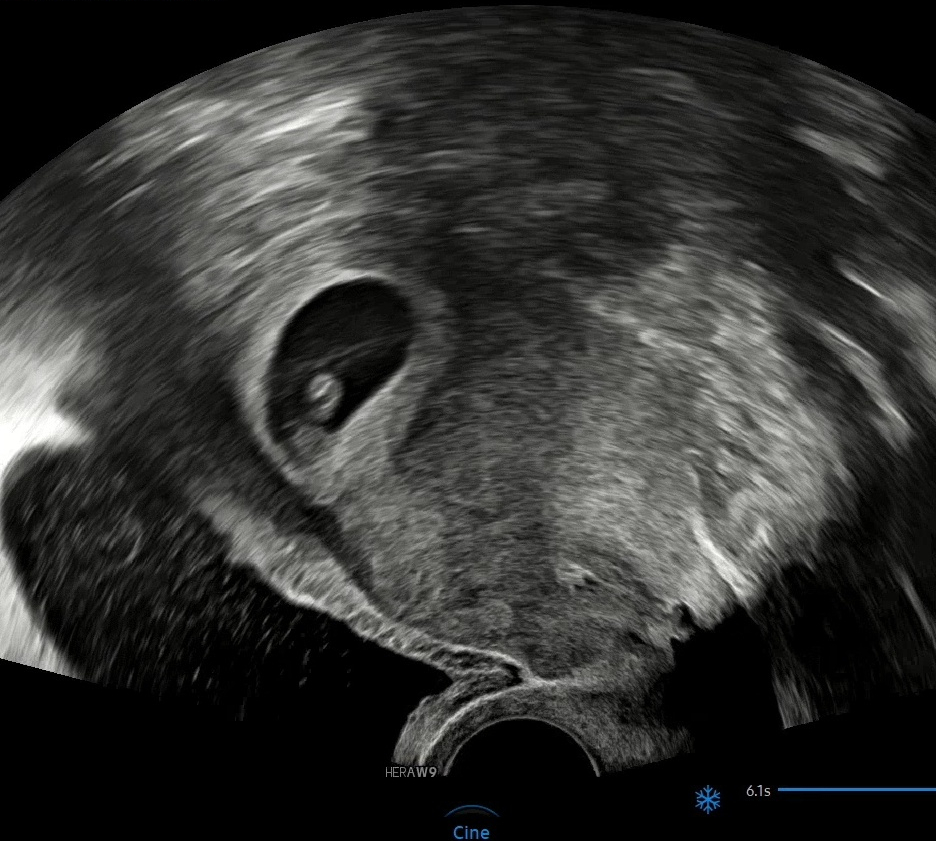

👆 드디어 하리보 아기 젤리 곰을 볼 수 있던 8주👆

작은 쌀알에서 조금 큰 하리보 젤리가 되기까지

저도 도담이도 정말 열심히 각자의 최선을 다하고 있었던 것 같아요